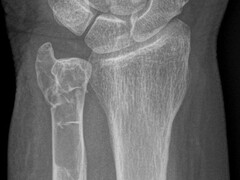

Beeldquiz

Stel je diagnose op basis van een foto. De wekelijkse beeldquiz van het NTVG is een leuke manier om je kennis snel te testen en te vergelijken met anderen.